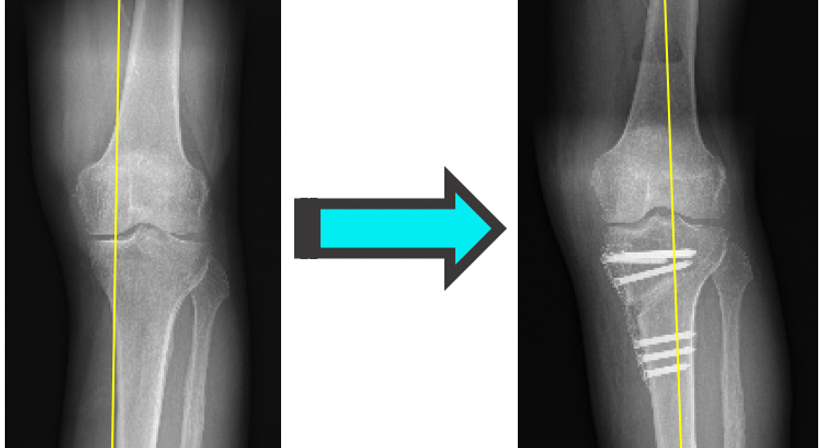

Beinachsenkorrektur / Umstellungsosteotomie

Eine nach innen oder außen gerichtete Fehlstellung der Beinachse wird typischerweise als X- oder O-Beinfehlstellung bezeichnet (Valgusknie bzw-. Varusknie). Eine X- und O-Beinstellung führt u.a. dazu, dass die Gelenkflächen des Knies ungleichmäßig beansprucht werden, wodurch es zu Überlastungsschäden wie Meniskusrissen und Knorpelabnützung kommt.

Insbesondere bei aktiven Patienten ist die Umstellungsosteotomie eine Möglichkeit

Beinachsenfehlstellungen zu korrigieren und somit Folgeschäden, wie z.B. Arthrose, zu vermeiden oder zumindest zu verzögern.

Im Gegensatz zum künstlichen Gelenksersatz (Knieendoprothese) ist die Ausübungen sämtlicher Sportarten nach einer Beinachsenkorrektur erlaubt. Die Korrektur wird meistens im Bereich des Schienbeins, in gewissen Fällen auch am Oberschenkel durchgeführt.

Durch moderne Operationsverfahren mit 3D- Planung und Korrekturschablonen aus dem 3D Drucker, sowie Fixierungstechniken (Plattensysteme) kann das Bein bereits am Folgetag nach einer Umstellungosteotomie wieder belastet werden. Der Krankenhausaufenthalt beträgt in der Regel 2-3 Tage.